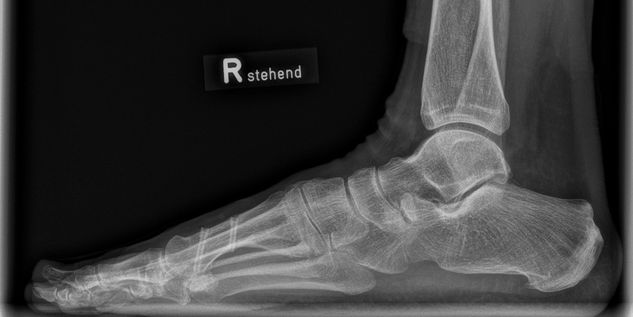

Implantate | Fuß

HBS 2 Resorb Mg und mm.CS

Nach über 100.000 erfolgreichen HBS- und HBS 2-Implantationen weltweit startet eine neue Ära mit der Erweiterung des Angebots um HBS 2 Resorb Mg Kompressionsschrauben. Diese innovative Schraube aus einer speziellen Magnesiumlegierung behält die bewährte HBS 2-Geometrie bei und ist nun zudem bioabsorbierbar. Auf diese Weise bleibt dem Patienten eine zweite Operation zur Metallentfernung erspart.

Magnesiumimplantate durchlaufen im Körper einen kontrollierten Abbauprozess, bei dem das Implantat in Knochen umgewandelt wird und Wasserstoffgas freigesetzt wird. Eine spezielle Oberflächenumwandlung verlangsamt die Korrosion des Implantats, wodurch die Abbaurate vermindert wird, was entscheidend für die Frakturheilung und die Integration des Implantats in das Knochengewebe ist.

Unser resorbierbares Schraubenportfolio, bestehend aus HBS 2 Resorb und mm.CS Implantaten unseres Kooperationspartners medical magnesium enthält kanülierte, kopflose Kompressionsschrauben in fünf verschiedenen Durchmessern. Dies ermöglicht den Einsatz in einem weiten Indikationsspektrum. Alle Schrauben sind selbstschneidend und können mit den bekannten und bewährten Operationstechniken eingesetzt werden. Lediglich das Kopfraumfräsen wird als zusätzlicher Operationsschritt ergänzt, um das Eindrehmoment beim Implantieren zu reduzieren.